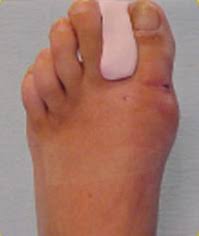

Zur Behandlung und Therapie des Hallux Valgus sowie zur Linderung der Schmerzen gibt es verschiedene Methoden. Sie hat sich direkt operieren lassen da man es empfohlen hatte. Als letzte Option wird bei bereits stark verformten Zehen meist eine Operation durchgeführt. Auch sehr stark ausgeprägte Fehlstellungen können meist nur noch operativ korrigiert werden. Aufgrund von Schmerzen schaffen sich Patienten mit einem Hallux valgus oft weiches breites Schuhwerk an. Neben der Verformung sind Schmerzen Beeinträchtigung der Nachbarzehen mit Hammerzehenbildung und chronische Entzündungen die Folge. Kann ich beide Füße gleichzeitig operieren.